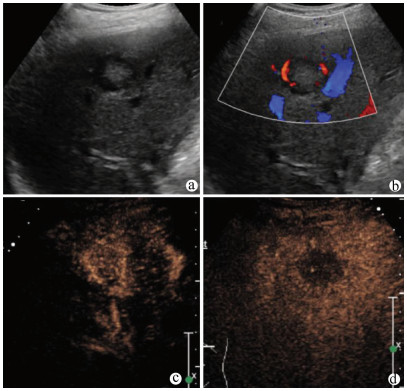

Guideline for ultrasonic diagnosis of liver diseases

Chinese Society of Ultrasound in Medicine, Oncology Intervention Committee of Chinese Research Hospital Society, National Health Commission Capacity Building and Continuing Education Expert Committee on Ultrasonic Diagnosis

2021, 37(8): 1770-1785. DOI: 10.3969/j.issn.1001-5256.2021.08.007

Abstract(3025) HTML (6526) PDF (9311KB)(794)

Abstract:

Ultrasound is a non-invasive, real-time, inexpensive, radiation-free and easily repeatable method, usually used for liver imaging. In recent years, new ultrasound examination techniques for liver diseases such as contrast-enhanced ultrasound and elastography have been rapidly developed, which can effectively identify intrahepatic space-occupying lesions, assess the degree of liver fibrosis and portal hypertension, and monitor the effects of treatment. Therefore, these technologies play an important diagnostic role in clinical liver diseases and have therapeutic interventional value. This guideline classifies the instrument set-up, patient preparation, and physician examination methods through multimodal ultrasound examinations (gray-scale ultrasound, color Doppler ultrasound, contrast-enhanced ultrasound, elastic ultrasound) for liver diseases. In addition, liver diseases multimodal ultrasound technology diagnostic criteria for diffuse hepatic lesions (inflammatory lesions, fibrosis, and sclerosis), multiple space-occupying lesions, and interventional procedures have been defined and standardized. Concurrently, we also recommend the ultrasound monitoring time interval and diagnostic report writing standard for liver diseases.